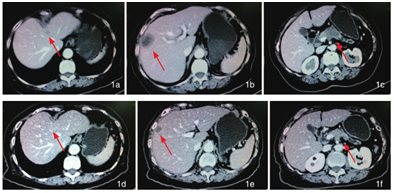

2013年6月,李女士发现胰腺癌合并梗阻性黄疸,且有肝、肺等处多发转移。在广州某著名肿瘤医院就医,医生告诉患者和亲属:晚期胰腺癌合并肝肺等器官多发转移,已没有治疗手段和价值,建议回家给予止痛、助消化等对症减轻患者痛苦,患者生存期只有3个月左右。不愿意就此放弃的家属通过网络,来到广州中医药大学金沙洲医院。到院后,进行CT检查发现:胰腺癌已累及整个胰腺,同时转移至左肺上叶、肝脏和腹腔等多处淋巴结。广州中医药大学金沙洲医院肿瘤专家组为其制定个性化治疗方案,先应用海扶刀(高强度聚焦超声)对整个胰腺进行分次分段的局部靶向热消融,同时进行P53基因全身热疗。

上图为治疗前CT,下图为治疗后CT

三次海扶刀和全身热疗后,原本越来越重的腰背部疼痛明显减轻,一周后病人不再需要服用止痛药,二周后B超常规检查不断显示胰腺肿块逐渐缩小,每月一次的CA199等胰腺癌各项指标都在下降,体重增加、精神状态和生活质量越来越好。在治疗前,特别让病人恐怖的化疗副作用,完全没有出现。

2013年9月初,经过两个疗程的海扶刀+P53基因全身热疗,经CT检查发现:胰腺肿瘤大部分消失,肝转移病灶消失、肺转移病灶、腹腔淋巴结转移灶基本消失,患者达到临床治愈的效果。目前已过2年,李女士仍然存活,在家中操持家务,享受天伦,在健康状态下生活。